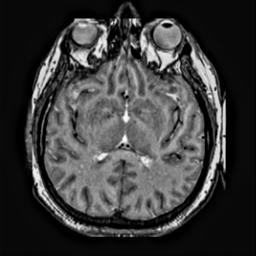

To demonstrate the effectiveness and efficiency of the proposed image fusion method , we conduct a set of comparative experiments on three image datasets. The first is composed by 8 pairs of multi-modal medical images and the second one contains 15 pairs of multi-focus gray or color natural images. These two datasets are often used in many related papers and some examples are shown in Figure 3(a) and Figure 3(b). The third one is a new multi-focus cervical cell image dataset collected by ourselves, which consists of 15 groups of color images and each group contains a series of multi-focus cervix cell images with size of or , etc. Some source examples are shown in Figure 3(c). Our source code implemented in C++ along with the new multi-focus cervical cell image dataset is available online.

We first evaluate the performance of the proposed method under varying total number of octaves and number of layers sampled per octave. The fused images of a pair of multi-modal medical images with different and are shown in Figure 4. In this example, on the one hand, when only 1 or 2 octaves are involved in constructing the DoG pyramid, the fused images fail to keep the integrity information of large size objects (e.g. eyeballs), while by increasing the value of , the integrity information of eyeballs is preserved. On the other hand, although not as significant as the increase of octave numbers , the fused image can contain more details by the increase of layer numbers . The corresponding objective quality metrics are shown in Figure 5. As shown in Figure 5(a), most of the metric values are improved as the number of octaves increases with the fixed layer numbers 3 in the global tendency and each of them tends to be stable when the number of octaves is 5. To get a relatively good quality from Figure 5(b), we can notice that some of the metric values can get a good performance when the number of layers is 3, such as the MI, SSIM, QI and VIF, though there are only a little change of all the metric values by increasing the number of layers with the fixed octave numbers 5. Because it will result in more computation burden with the increase of the value and , and for different kinds of source images, there are different performance with the diverse parameter settings. To get a trade-off between them in our experiments, we set for the multi-modal dataset, for the natural datasets and for the multi-focus cell dataset, respectively.

Figure 6 shows the fused images obtained by different methods with the multi-modal source images shown in Figure 3(a). As shown in these figures, the proposed method can produce images which preserve the complementary information of different source images well. Moreover, due to the scale-invariant structure saliency selection, our method can keep the integrity information of large size objects and the visual details simultaneously. Although the fused image generated by other methods can also capture the details to some extent, all of them fail to keep the integrity information of large size objects such as the eyeballs. Furthermore, from Figure 6(k)-6(t), the DTCWT, GFF, IM and NSCT methods may decrease the brightness and contrast while the proposed method can preserve these features and details without producing visible artifacts and brightness distortions.